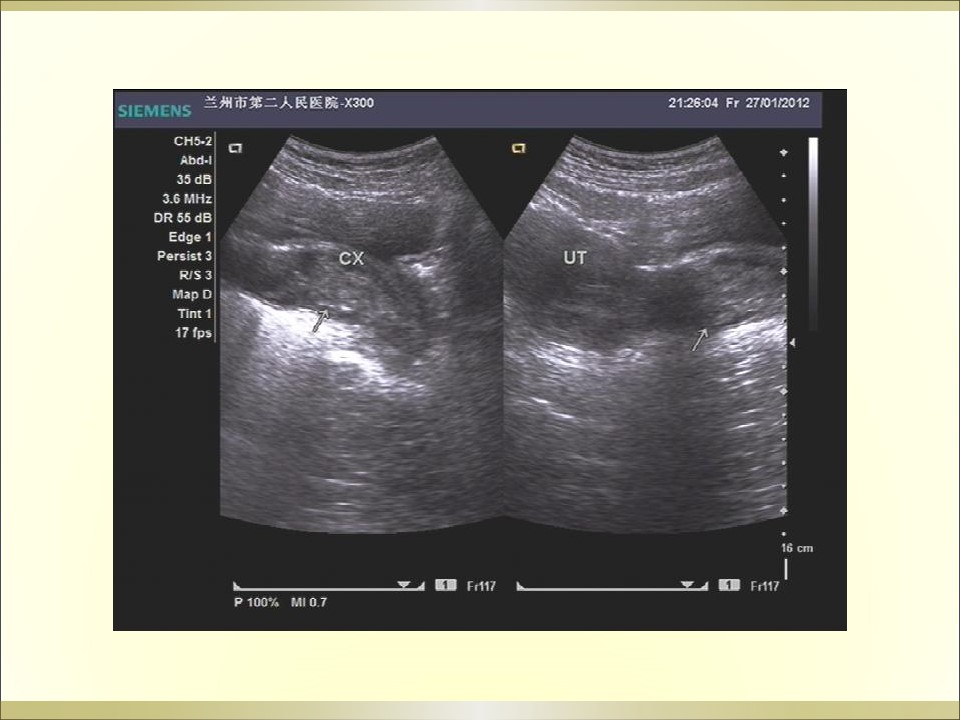

妇产科急腹症是指因妇科疾病引起的剧烈的急性腹痛,可以是原有疼痛突然加剧,或原无疼痛突然发生,是病因较多的常见病,特点是发病急、病变进展快、病情重,需要及时作出病因诊断及治疗。